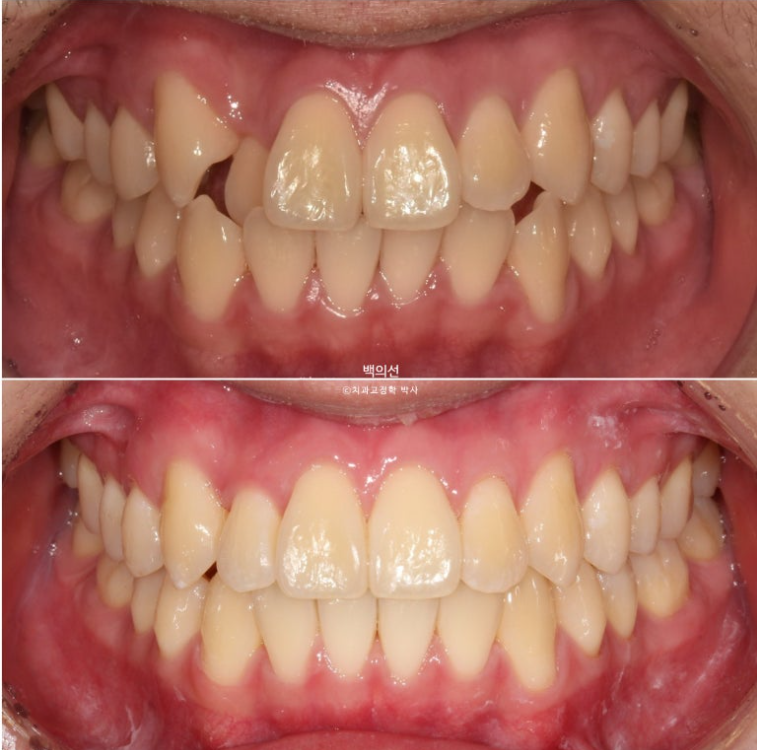

전 후 비교 보겠습니다.

24.04~25.07